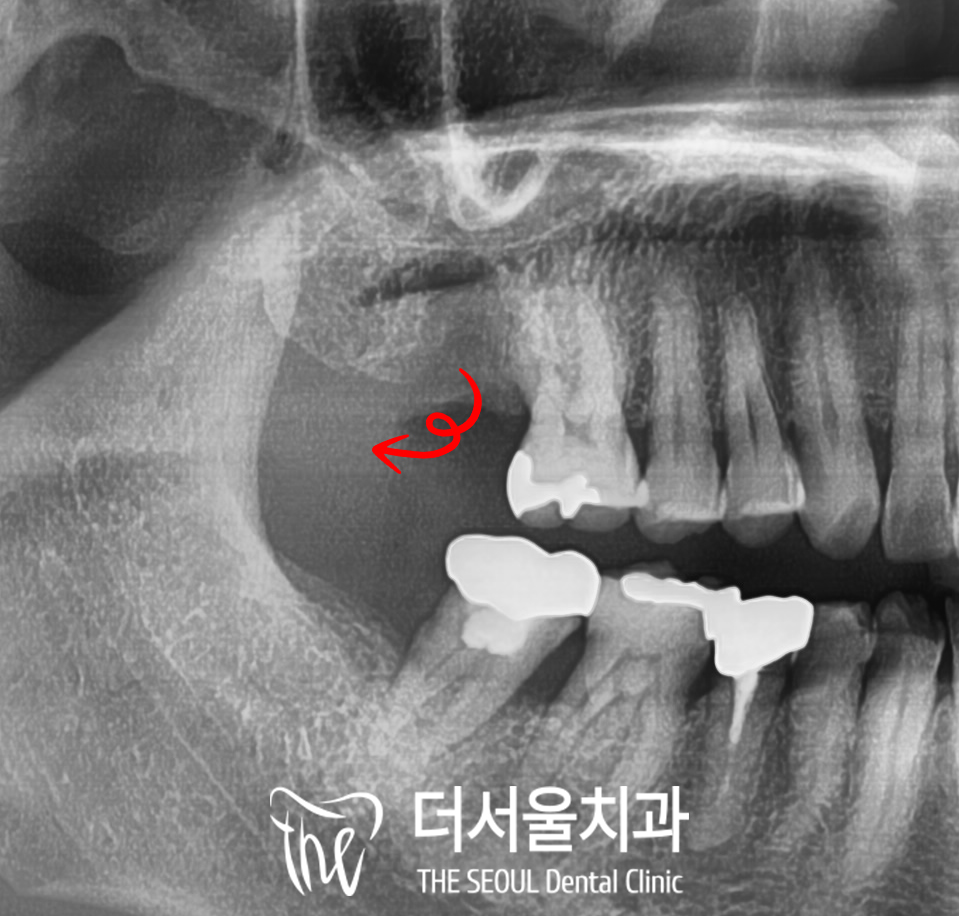

3. 상악동 뼈이식 필요

이 분 같은 경우

정밀진단을 통해 살펴보니

치조골 소실량이 매우 많은 편이라

디지털 임플란트를 심는 것만이

중요한 게 아니라

그 위쪽에 존재하는

‘상악동’을 잘 컨트롤하는 게

오늘 수술의 핵심이 되겠습니다.

그래서 심어질 픽스처의 사이즈를 고려하여

sinus lift라고 부르는

상악동을 들어 올리는 시술을

함께 진행했는데요,